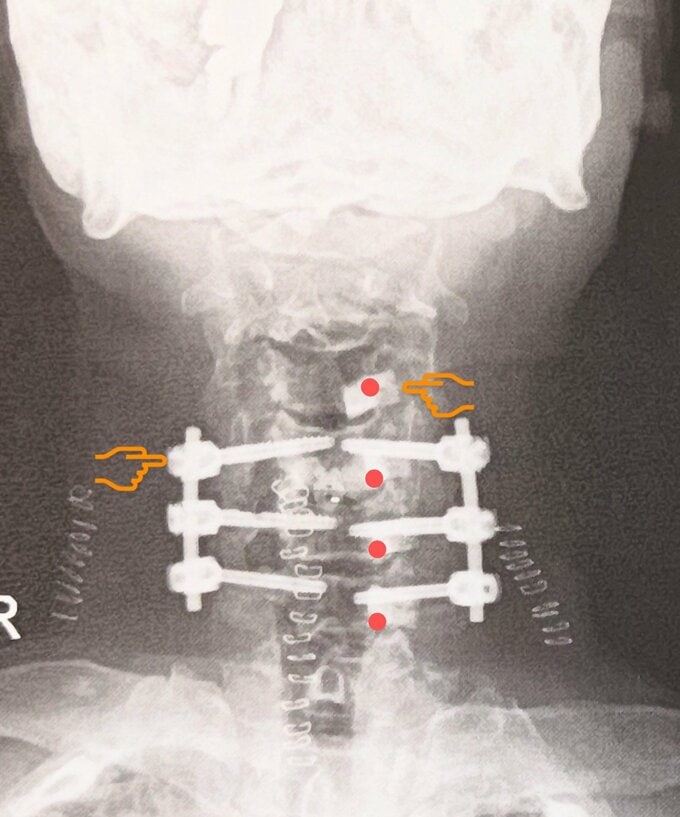

巨人さんは「昨日10日で頚椎術後.半年…こんなしんどい辛い半年に成るとは」と綴るとレントゲン写真をアップ。

投稿された画像では、巨人さんの首に複数のボルトが入っている様子が見て取れます。

最後に、巨人さんは「今 首には11個の人工物が」と、泣き顔の絵文字を添えて、その思いを綴っています。

そして、巨人さんは「首にボルトを6本入れる」「想定外の長時間の手術」「入院が予定より長く」と、当初の見込みより大幅に延びたことで、出演予定にも支障が出たことを関係者やファンに陳謝。次いで「術後 色々合併症が何ヵ所」「苦しんでおります 術前よりも数倍辛いです」と、綴っていました。